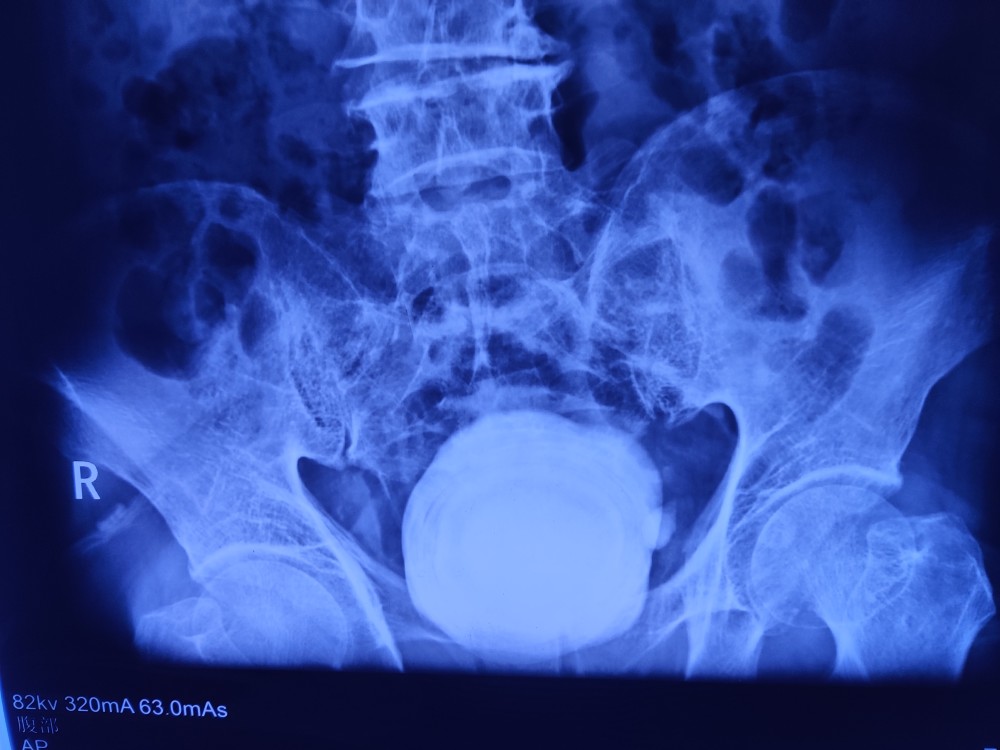

比鹅蛋都大的膀胱结石你见过么

膀胱巨大结石一例